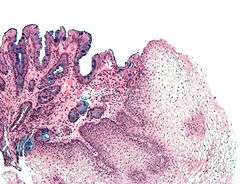

Both macroscopic (from endoscopy) and microscopic positive findings are required to make a diagnosis. Barrett's esophagus is marked by the presence of columnar epithelia in the lower esophagus, replacing the normal squamous cell epithelium—an example of metaplasia. The secretory columnar epithelium may be more able to withstand the erosive action of the gastric secretions; however, this metaplasia confers an increased risk of adenocarcinoma.[9]

Intestinal metaplasia

The presence of goblet cells, called intestinal metaplasia, is necessary to make a diagnosis of Barrett's esophagus. This frequently occurs in the presence of other metaplastic columnar cells, but only the presence of goblet cells is diagnostic. The metaplasia is grossly visible through a gastroscope, but biopsy specimens must be examined under a microscope to determine whether cells are gastric or colonic in nature. Colonic metaplasia is usually identified by finding goblet cells in the epithelium and is necessary for the true diagnosis.